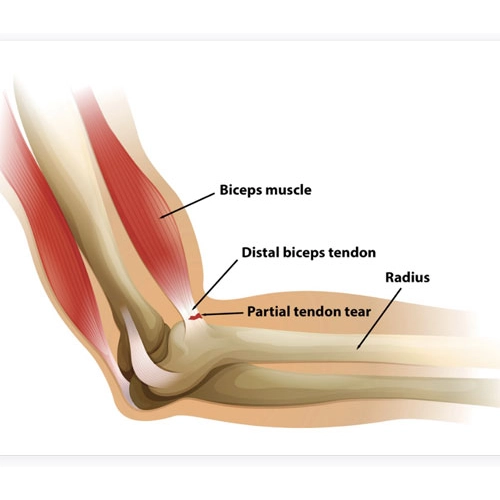

تاندونها، ساختارهای بافتی محکم و کشسانی هستند که عضلات را به استخوان متصل میکنند. در ناحیه آرنج، تاندونهای مختلفی وجود دارند که اصلیترین آنها عبارتاند از:

- تاندون دوسر بازویی (Biceps Tendon)

پارگی این تاندونها ممکن است بهصورت کامل یا جزئی رخ دهد و معمولاً در اثر فشار بیشازحد، ضربه مستقیم یا حرکات ناگهانی اتفاق میافتد. در صورتیکه پارگی کامل باشد، عملکرد طبیعی مفصل دچار اختلال جدی خواهد شد.

پارگی تاندون معمولاً با درد تیز و ناگهانی در ناحیه آرنج یا بالای ساعد همراه است. این درد میتواند هنگام بلند کردن اجسام یا خمکردن بازو تشدید شود.

بیمار ممکن است نتواند بهدرستی بازوی خود را خم یا صاف کند. در موارد پارگی تاندون دوسر یا سهسر، کاهش قدرت عضلانی شدید دیده میشود.

۵. تغییر شکل ظاهری بازو

در موارد پارگی کامل، عضله جدا شده و به عقب جمع میشود که باعث ایجاد برجستگی غیرطبیعی یا گودی غیرعادی در بالای ساعد میشود.